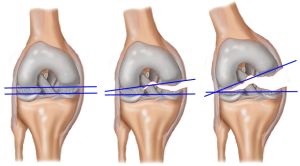

- un grad ușor (tibial și femurale suprafețele ale articulațiilor sunt decalate unul față de celălalt cu 5 mm, capsula este deteriorat parțial relaxat minim un aparat ligamentare);

- grad mediu. când această diferență variază între 5 și 10 mm (puternic cruciat prejudiciu ligament);

- severă. când indicatorul de deplasare depășește 10 mm (ruptura anterior sau posterior cruciat ligament, sau ambele).

În multe cazuri, instabilitate a genunchiului este mai convenabil să se calculeze nu în mm. și în grade.

Indicator deplasare ușoară nu este mai mică de 5 grade, de mijloc - de la 5 la 8 grade, grele - mai mult de 8 grade.